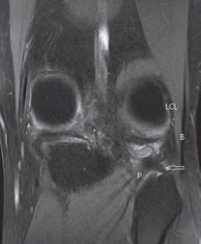

- Le muscle poplité est profond à la face postérieure du tibia (Fig. 2).

- La jonction myotendineuse se fait souvent par deux lames tendineuses convergentes (Fig. 3). Ces dernières seront vues au mieux sur des coupes coronales. Puis, le tendon rejoint la fossette du poplité (Fig. 4), au bord latéral du condyle, en passant dans le hiatus poplité puis sous le ligament arqué (Fig. 5).

- Les faces supérieure et inférieure du hiatus poplité sont constituées par les ligaments ménisco-poplités supérieur et inférieur. Le tendon du poplité est lié à la fibula par le ligament poplitéo-fibulaire (Fig. 6).